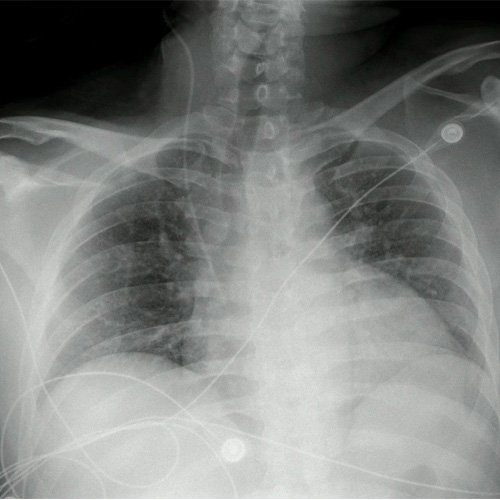

• Radiografía de tórax (Día 0): rotada, sin consolidación pleuroparenquimatosa. Senos costofrénicos libres. Cateter de vía central en aurícula derecha.

Radiografía de tórax al ingreso (Día 0)